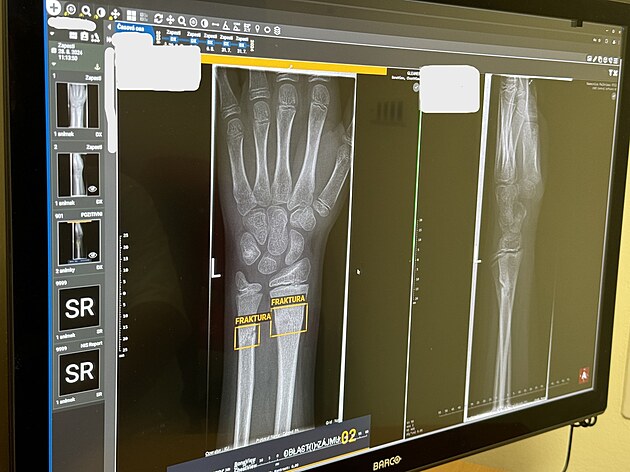

Nemocnice Pelhřimov po půlročním testování úspěšně zavedla využívání umělé inteligence na svém radiodiagnostickém oddělení.